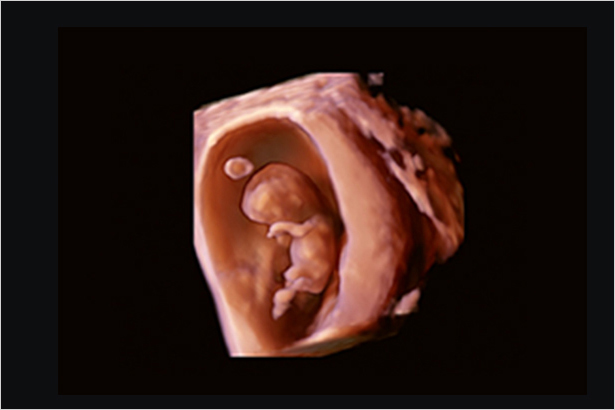

根據胎兒的容積數(shù)據,可以半自動地測量大腿或者上臂的部分體積,然后根據測量結果推斷出估計體重 EFW。

在水平方向和垂直方向掃描,并從連續(xù)采集的動態(tài)圖像數(shù)據中重建三維圖像。通過設置擺動操作的角度或滑動操作的距離,可以輕松地重建容積圖像。